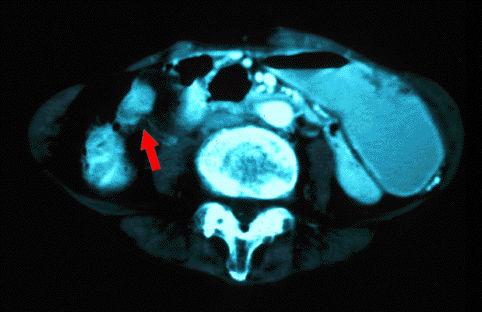

clasificación del pacienteTumor Epitelial Maligno/Otros

parte(separada por órganos)otros/

método de exámenTAC

múltiples tumores(en varios órganos)presente(simultáneo)